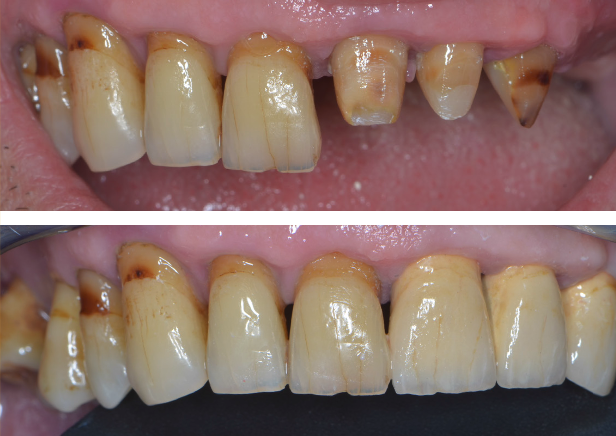

Lucrările pot fi realizate, în funcție de caz, pe ambele maxilare sau doar pe unul dintre maxilare. Atunci când pacientul prezintă lucrări vechi necorespunzătoare, sprijinite pe dinți care prezintă mobilitate crescută, (Fig. 3.6.1 lucrarea anterioară, mandibulară și Fig. 3.6.2) pacientul va rămâne edentat (fără dinți) în urma extracțiilor dinților mobili. În cazul acestui pacient, toți dinții superiori prezintă rectracții ale gingiei, iar cei din partea stângă (incisivul central, incisivul lateral și caninul) au fost tratați endodontic (tratamente de canal). Acest lucru a indicat acoperirea lor cu coroane metalo-ceramice (Fig. 3.6.3).

Pe baza scanărilor imagistice 3D (CBCT) se vor efectua măsurători ale înălțimii și lățimii osului mandibular, astfel încât medicul implantolog să poată decide dacă se pot insera implanturi direct sau este nevoie de adăugare de os în prealabil. Se realizează un ghid chirurgical care ajută la poziționarea precisă a implanturilor în os (Fig.3.6.4. dr. Ondine Lucaciu), iar în 24 de ore după această intervenție pacientul primește o punte provizorie fixă pe care o va purta un interval de 3-6 luni, perioadă necesară osteointegrării implanturilor, respectiv vindecării (Fig. 3.6.5). Această lucrare provizorie va fi înșurubată în 6 puncte, în cele 6 implanturi inserate în mandibulă (Fig. 3.6.6).

După acest interval lucrarea provizorie se îndepărtează, în fiecare implant se montează câte un dispozitiv necesar realizării amprentelor (Fig. 3.6.7) care vor servi tehnicianului dentar pentru realizarea punții definitive (Fig. 3.6.8 și Fig. 3.6.9). Realizarea acesteia se face în câteva zile, interval în care pacientul va continua să poarte lucrarea provizorie realizată inițial.